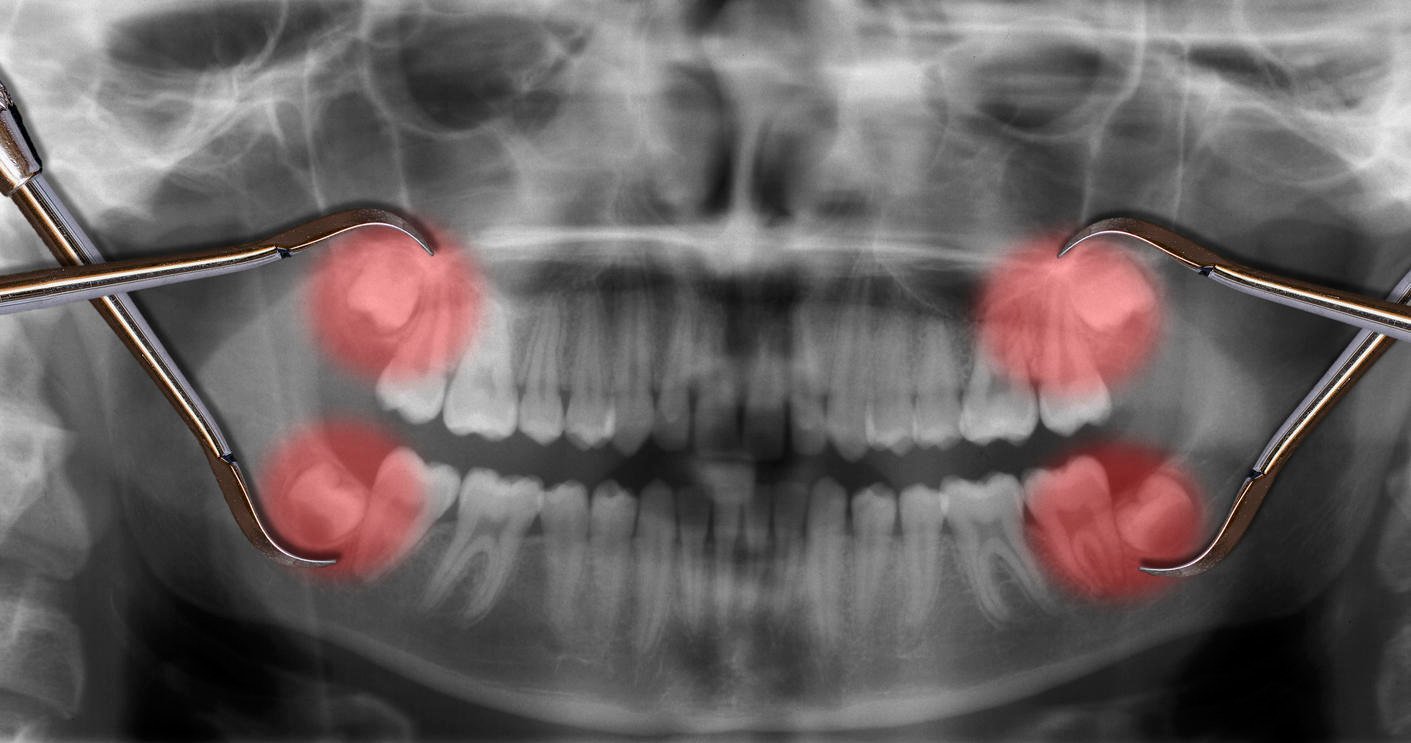

afficher quatre dents de sagesse sur une radiographie

Réputées pour les vives douleurs qu’elles peuvent occasionner, les dents de sagesse sont les troisièmes molaires. Elles poussent généralement pendant l’adolescence ou à l’âge adulte, entre 16 et 25 ans. Chez certaines personnes, elles n’apparaissent jamais. La percée des dents de sagesse est parfois douloureuse et s’accompagne d’une inflammation.

La radiographie panoramique et la palpation permettent au dentiste d’estimer la sortie des dents de sagesse et le rythme de leur croissance. Les informations obtenues ne sont pas fiables à 100 %, mais l’expérience personnelle de chaque dentiste permet généralement de prendre la bonne décision.